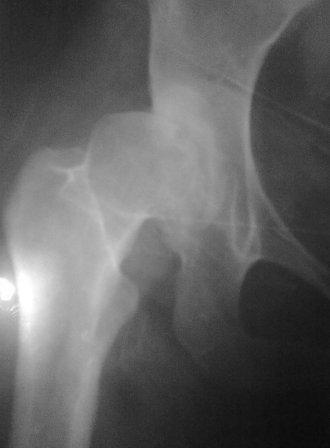

Диспластический коксоартроз

Уважаемые коллеги! Обратилась б-ная 26лет с сильными болями в лев. т/б суставе,

оказалась в 2х летнем возрасте лечилась у меня по поводу врожд.вывиха бедер. Боли начались 2 года назад после второй беременности. Сгибание в т/б суставе 90градусов,разгибание-10,отведение-30.приведение - 10, внутрен.ротация - 20., наруж. ротация - 10. при отведении и ротации боли усиливается. Направил в НИИТО, где ей предлагали эндопротезированию, но финансовые возможности не позволяет.

Предварительный план: учитывая неплохое функциональное состояния т/б сустава межвертельная укорачивающая, варизирующая и возможно деротационная остеотомия с фиксацией клинковой пластиной, или PF БИОС (по предварительным скиаграммам и КТ)